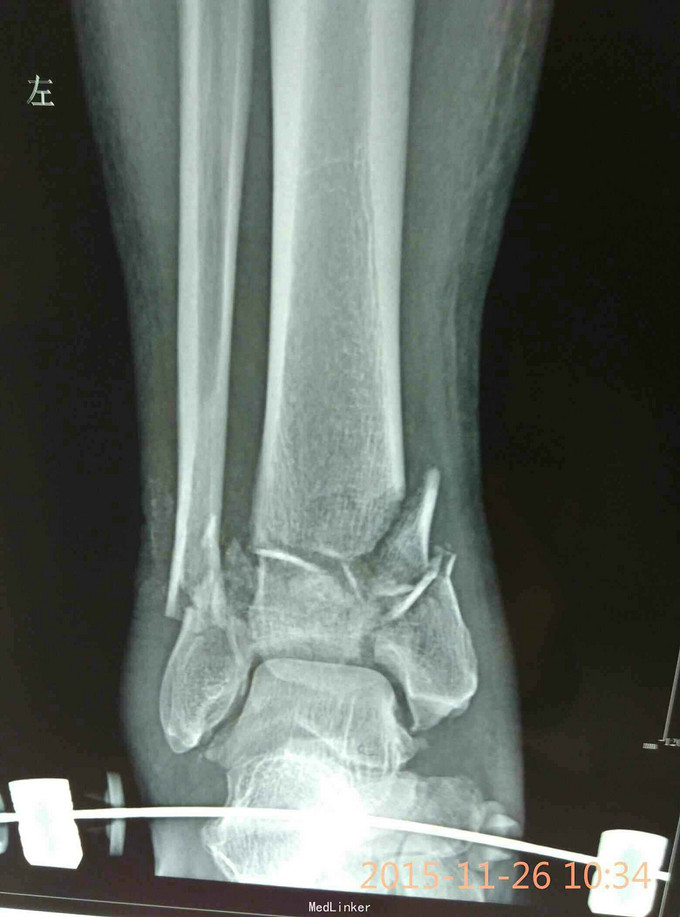

Pilon骨折,牵引10天

车祸致伤,开放性,急诊复位,跟骨牵引,清创,抗炎对症,伤口愈合可,无感染迹象,欲手术治疗,请各位老师给点建议。

伤时左踝畸形肿胀,外踝上方见长约5cm不规则裂伤,骨端外露,踝关节功能丧失,足背动脉搏动有力

左侧Pilon骨折于急诊清创骨折复位缝合并行跟骨牵引治疗。欲10天后,皮肤条件允许后,限期手术

选择何种术式,内固定物?